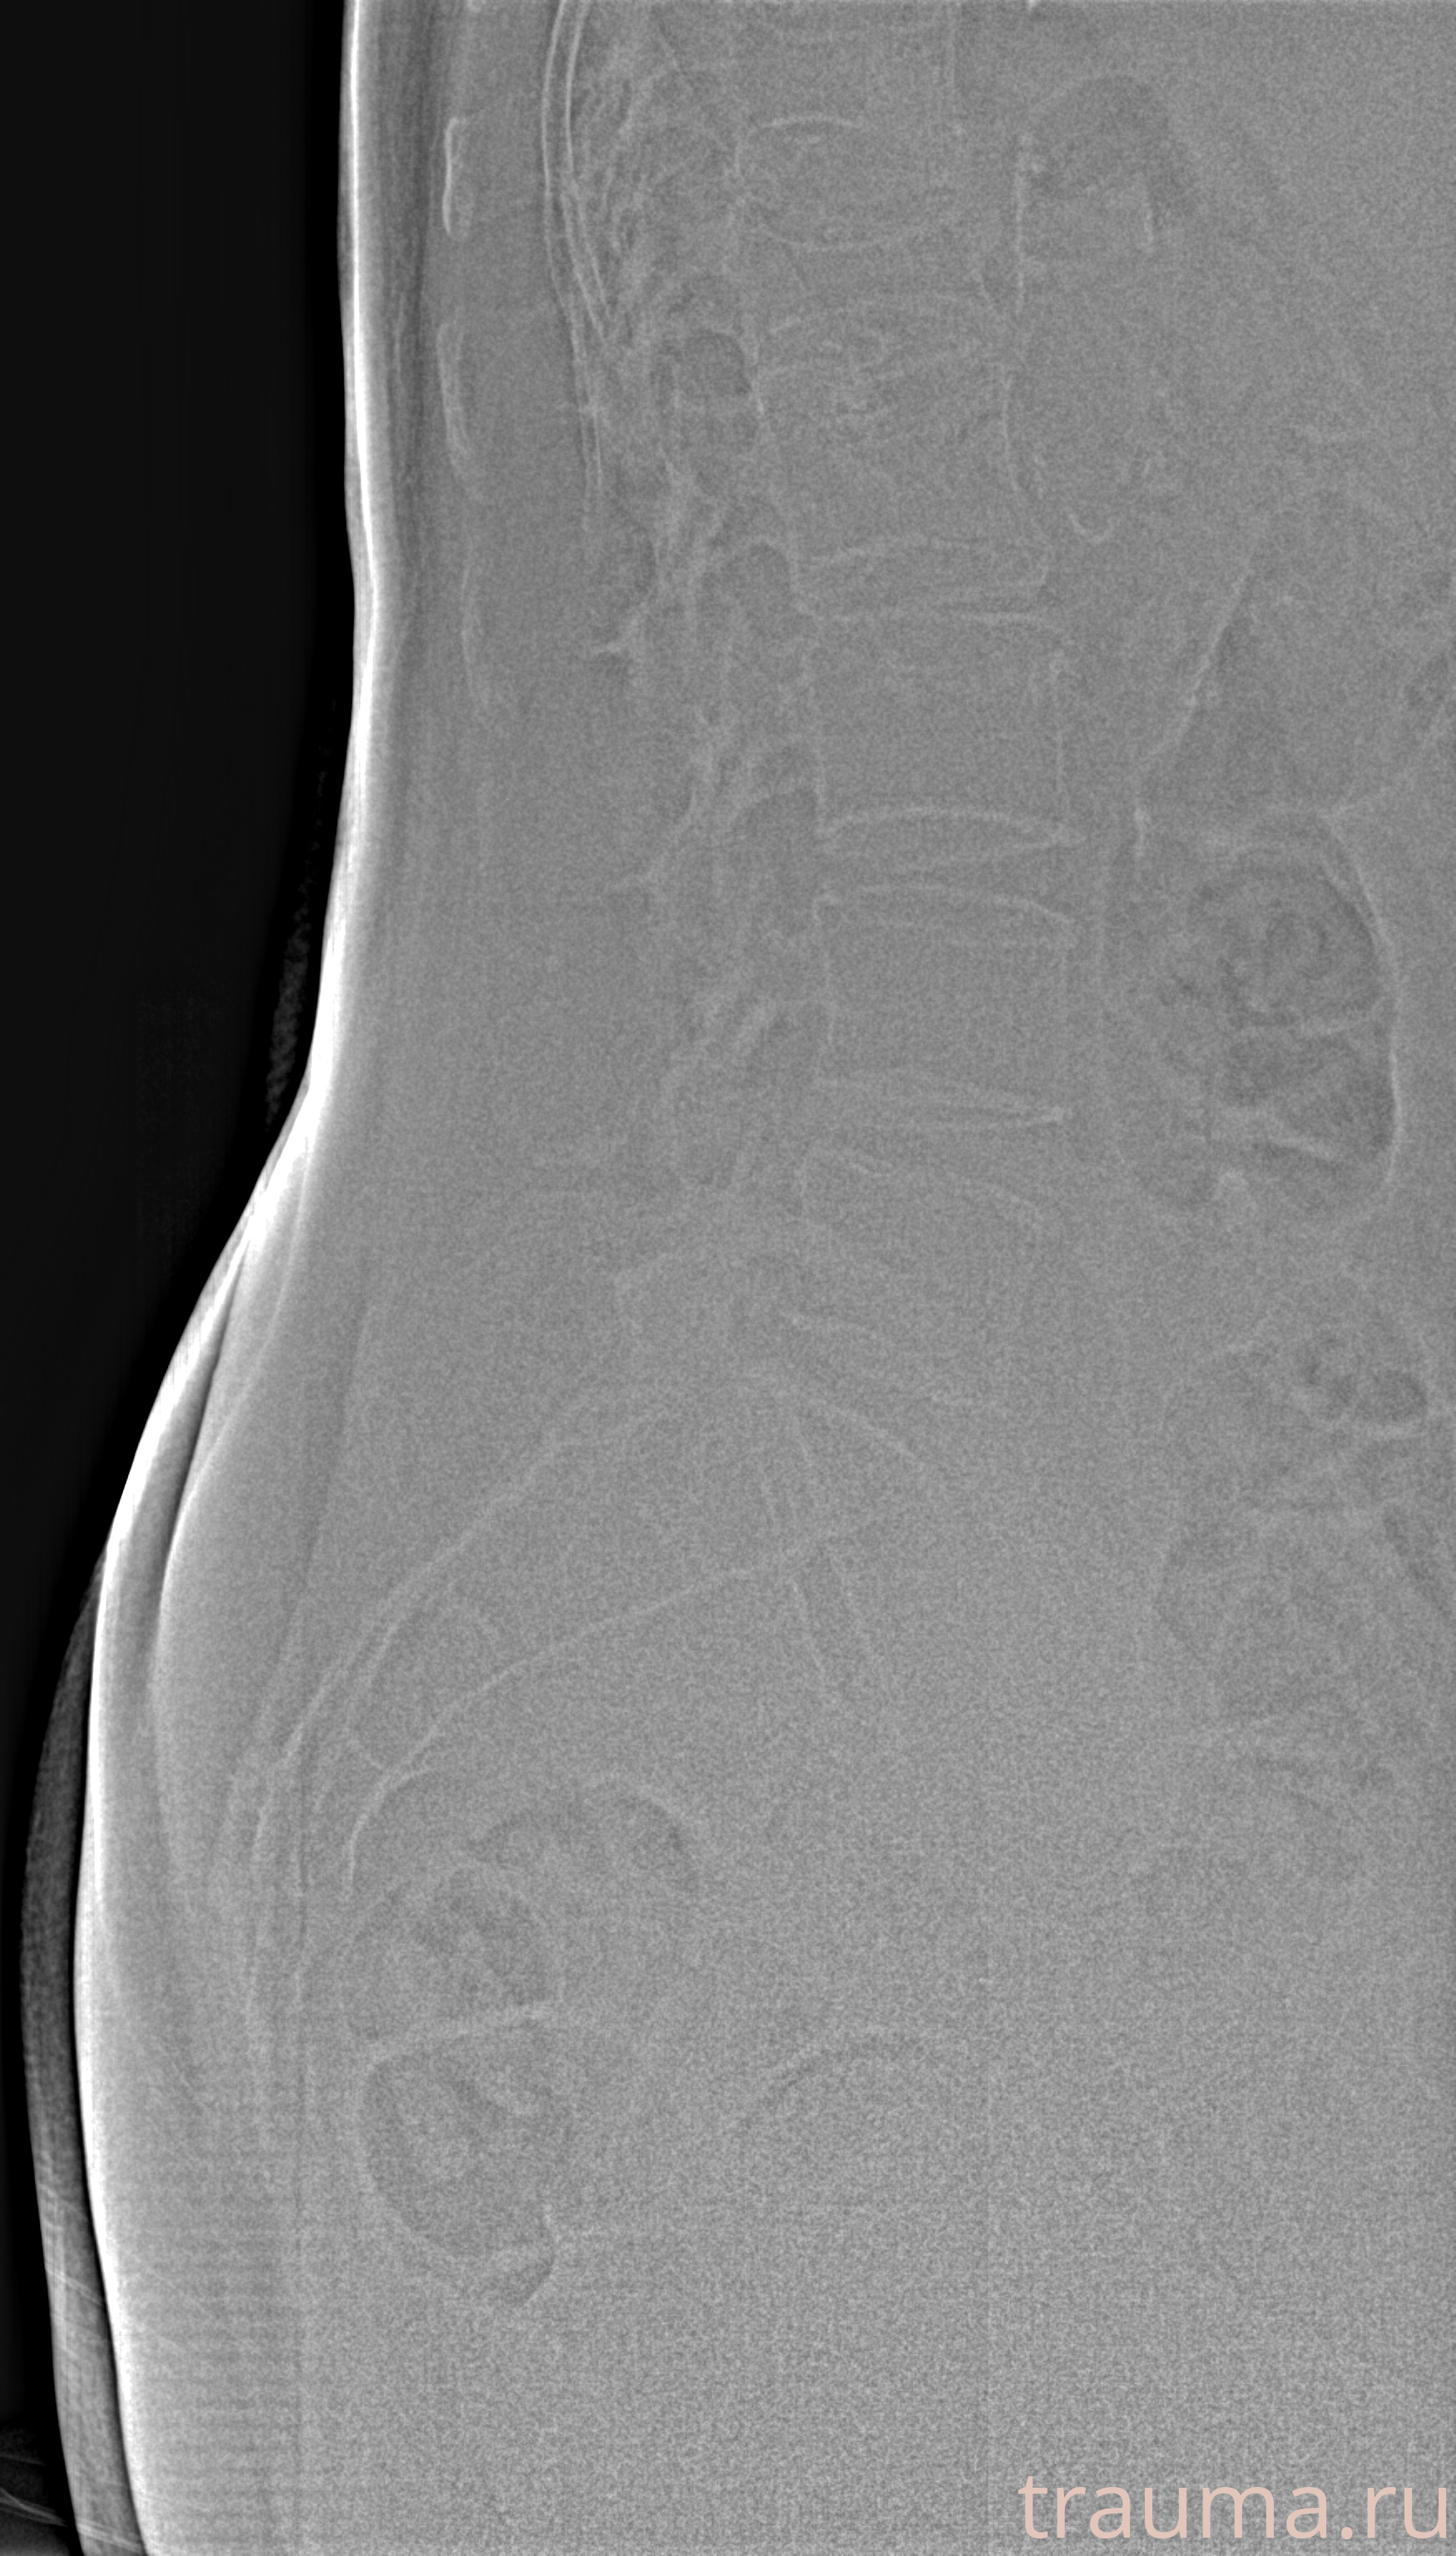

/  Невлянинова

Рентгенограммы

Рентген на дому: по вашему адресу приезжает врач-рентгенолог, травматолог-ортопед с мобильным рентгеновским аппаратом, проводит диагностику травмы или заболевания, делает необходимые рентгенограммы, дает рекомендации по дальнейшему лечению. Получить качественные снимки в домашних условиях возможно благодаря уникальной методике, разработанной МосРентген Центром для института  Склифосовского